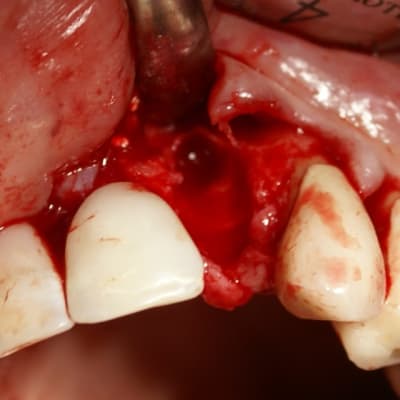

Tout à fait d'accord growler et c'est d'ailleurs ce que l'on peut voir sur le cas suivant. Fracture radiculaire, aucune infection periradicualire. Extraction et implantation immediate. Espace existant entre l'implant et l'alvéole est comblé par du BioOss. Un logement sous gingival est formé en vestibulaire et palatin de facon à pouvoir recouvrir le tout par BioGide et un conjonctif enfoui.

L'implant est de 15mm mais l'alvéole était large et 50% environ de la surface implantaire n'était en contact qu'avec du BioOss. J'ai pour cela préféré enfouir.